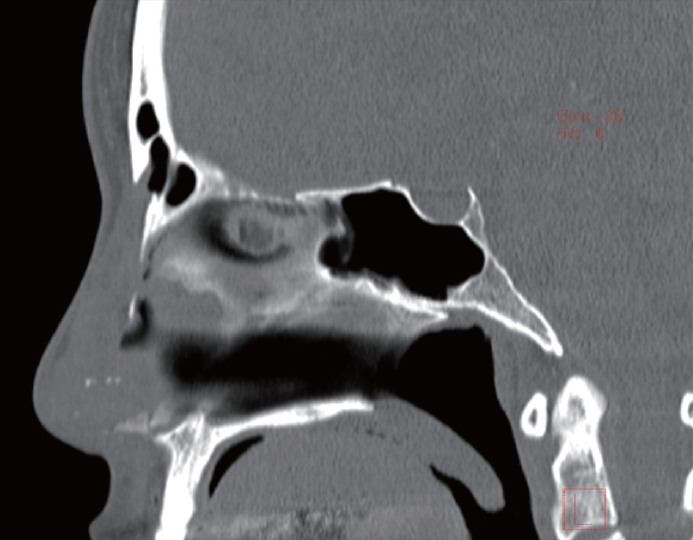

Follow-up sagittal CT scans obtained approximately 2 months postoperatively confirmed that the reconstruction of the bony defect on the left bony dorsum, repaired with homologous fascia, ear cartilage, fibrin glue was stable. There were no signs of inflammation or fluid collection within the frontal sinus (Fig. 5).